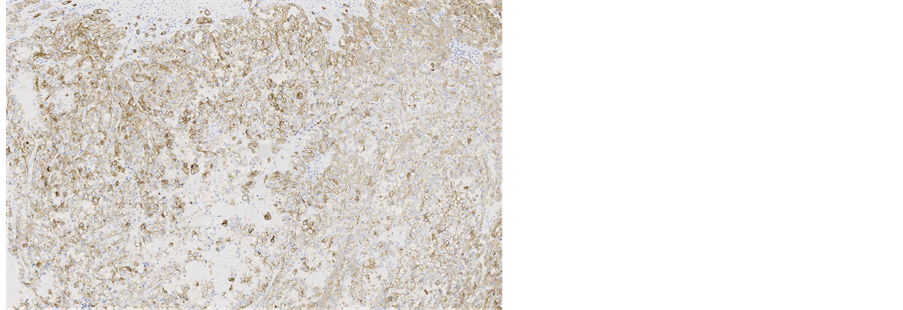

Immunohistochemical staining showed, that the tumour cells were diffusely positive for monoclonal antibodies against pancytokeratin (AE1/AE3) (Figure 5), cytokeratin 7 was positive in 5% of tumour cells (Figure 6), other markers, which showed immunoreactivity: EMA (5%), RCC-smp314 (30%), CA-125 (30%), p53 (was expressed weakly) (Figure 7), AMACR (diffuse positivity), CD10 (50%), Cyclin D1 (40% - 50%) and bcl-2. The tumour cells were negative for Vimentin (Figure 8), WT1 (Figure 9), Cytokeratin 20, ER/PR, CEA (Figure 10), TTF-1, CD57.

Figure 5. Microscopic appearance of the endometrial tissue from curetting specimen-clear cell carcinoma, immunohistochemical staining with monoclonal antibodies against pancytokeratins AE1/AE3, ×10.